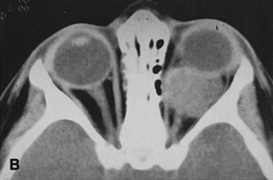

Valuable information about the nature and extent of an orbital pathologic process is provided by imaging studies such as computed tomography (CT) scan, magnetic resonance imaging (MRI), and orbital echography. Better spatial resolution, ready accessibility, and lower cost make CT the preferred choice for orbital imaging in most cases. Orbital fat provides a natural contrast between most adjacent orbital structures on CT scanning, and orbital bones are visualized well. Computed tomography is essential for evaluation of the orbital bones because they cannot be imaged with MRI. Direct coronal or sagittal images are important to identify the relationship of a lesion to the optic nerve so that the surgical approach can be planned to avoid traversing the optic nerve (Fig. 1).

Fig. 1. A. Axial CT scan demonstrating a large, well-encapsulated lesion in the orbital apex. Coronal (B) and sagittal (C) scans demonstrate that the mass lies inferior and medial to the optic nerve within the intraconal space. This information is useful in planning the surgical approach to the mass, which should avoid traversing the optic nerve.